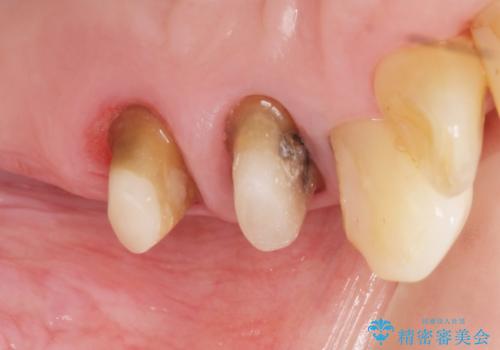

精査したところ、左上の大臼歯2本(左上67)が欠損しており、左上の小臼歯2本(左上45)は根が短く動揺があり根尖病変を認めました。

相談を重ねた上で小臼歯2本の再根管治療と連結補綴を行いました。

大臼歯がないため小臼歯に負担がかかりやすいことによるリスクを説明し、ご理解頂いた上で治療を行いました。